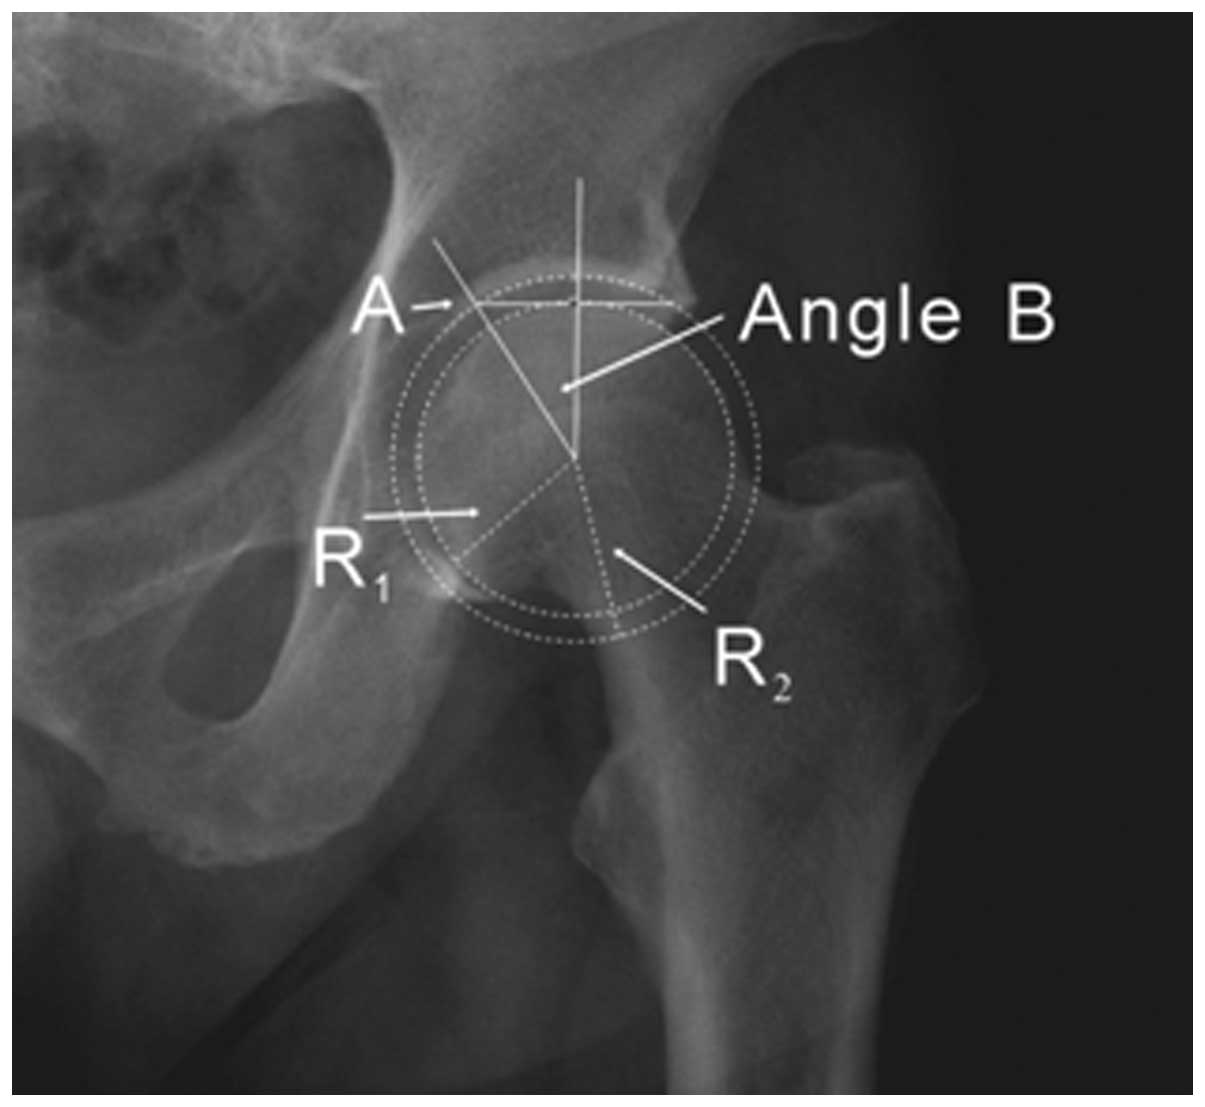

Figure 4

Radiograph showing the relative position of point A. Point A is used to measure the modified Tönnis angle, and the relative position of point A is determined by angle B. R1 and R2 represent the radii of the femoral head and acetabulum, respectively. Theoretically, cosB = R1/R2; therefore, the relative position of point A can only be affected by the radii of the femoral head and acetabulum.

Theoretically, the value of angle B is only affected by the radii of the femoral head and acetabulum

To improve the Tönnis angle, the modified Tönnis angle was created, which was formed by two lines that intersected at a point marked ‘A’ (Fig. 1C). Point A was used to measure the modified Tönnis angle, and the relative position of point A was determined by angle B (Fig. 4). R1 and R2 represented the radii of the femoral head and acetabulum, respectively. Theoretically, cosB is equal to R1/R2; therefore, the relative position of point A can only be affected by the radii of the femoral head and acetabulum. Compared with the medial edge of the acetabular sourcil, point A was clear in all patients, and its relative position was more stable. These data suggested that point A could rarely negatively affect the measurement of the modified Tönnis angle.